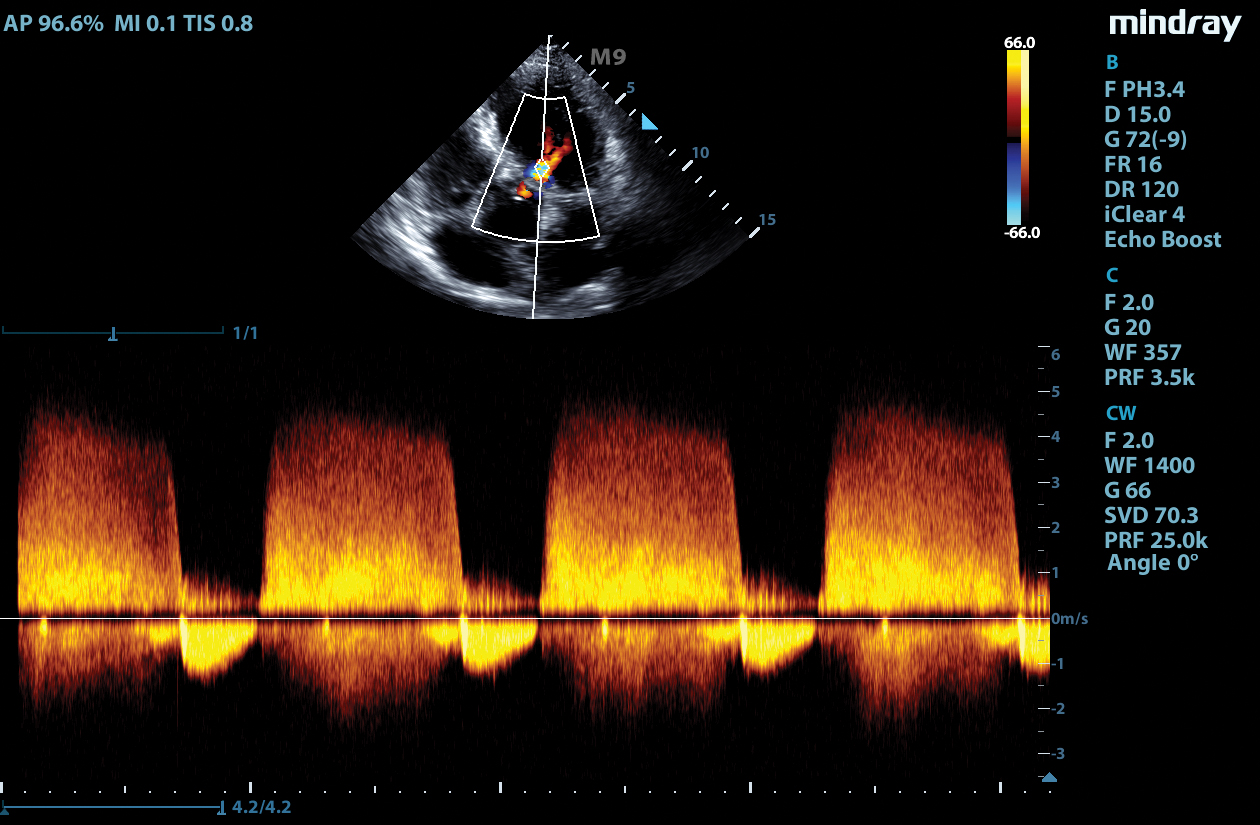

LVO with Stress Echocardiography

The combination of LVO during stress examinations enhances differentiation between tissue and the blood pool, providing better visualization of the endocardium. This package includes customizable user protocols, flexible wall motion scoring, and a comprehensive reporting suite.

Tissue Tracking

Mindray’s Tissue Tracking technology with quantitative analysis allows users to monitor the displacement of cardiac tissue by tracking the speckle displacement in the image from frame to frame. This non-angle dependent tool with onboard analysis, can be performed at the bedside, saving time and simplifying challenging cases.